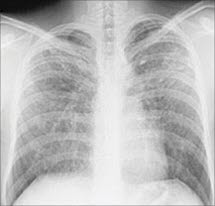

Sarkoidose i lungeneSarkoidose er en sykdom som kan angripe mange organer i kroppen. Den typiske forandringen er en knuteliknende betennelse (granulomatøs betennelse) som kan finnes i ulike organer. Sarkoidose finnes som oftest i lungene og i lymfeknuter i lungehulen (hiluskjertlene), men forandringer utenfor brysthulen er hyppige. De vanligste lokalisasjonene der man finner betennelsen, er foruten i lungene, i hud, øyne, sentralnervesystemet, skjelettet og hjertet.